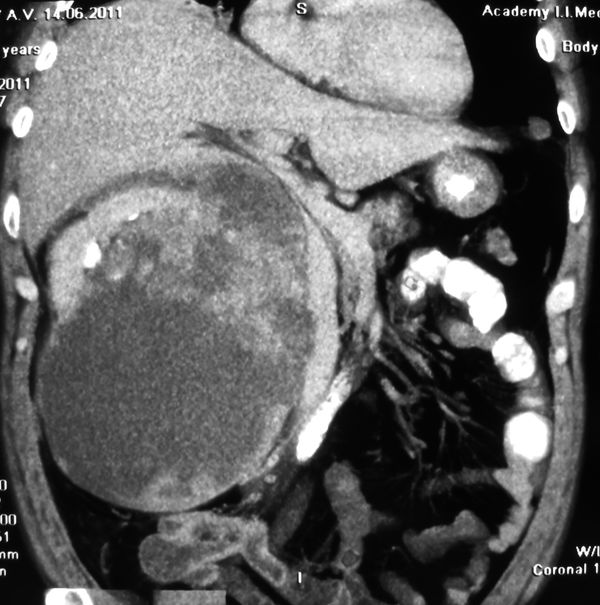

Огромная опухоль правой почки

Гигантская опухоль правой почки. Экстримальная нефрэктомия.